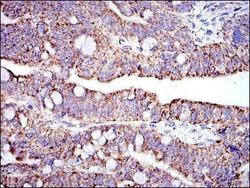

- Submitted by

- Novus Biologicals (provider)

- Main image

- Experimental details

- Immunohistochemistry-Paraffin: Prohibitin Antibody (5H7) [NBP2-37563] - Immunohistochemical analysis of paraffin-embedded liver cancer tissues using PHB mouse mAb with DAB staining.

- Submitted by

- Novus Biologicals (provider)

- Main image

- Experimental details

- Immunohistochemistry-Paraffin: Prohibitin Antibody (5H7) [NBP2-37563] - Immunohistochemical analysis of paraffin-embedded lung cancer tissues using PHB mouse mAb with DAB staining.